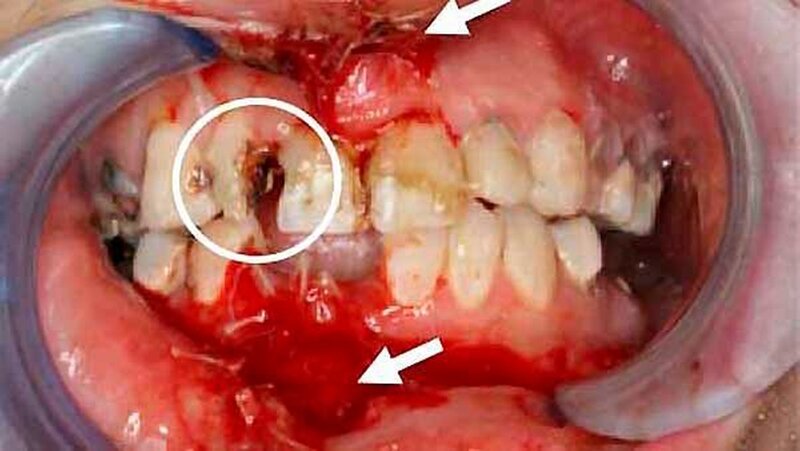

Eine 26-jährige Frau wurde nach einem Fahrradunfall in Begleitung der Polizei in unsere interdisziplinäre Notfallaufnahme mit multiplen und ausgeprägten extra- und intraoralen Weichteilverletzungen sowie einer Alveolarfortsatzfraktur des Ober- und Unterkiefers eingeliefert.

Die weitere klinische Inspektion ergab intraoral den Befund eines kariös tief zerstörten Restzahngebisses mit multiplen, teils gelockerten, nicht erhaltungswürdigen Zähnen.

) erfolgte in Vollnarkose eine Wundrevision und Reposition der Nasenbeinfraktur. Zusätzlich erfolgte - mit Ausnahme der dentes caninii - die operative Entfernung der tief zerstörten und nicht erhaltungswürdigen Restbezahnung des Ober- und Unterkiefers in Kombination mit einer modellierenden Osteotomie sowie einem plastischen, speicheldichten Wundverschluss.

), weiche Kost und Prothesenkarenz. Die histopathologische Aufarbeitung der entnommenen Knochenproben zeigte Anteile von nekrotischem Knochen, obwohl weder in der klinischen Inspektion, noch in der Bildgebung (OPG und CT) Anzeichen für eine Knochennekrose zu finden waren.